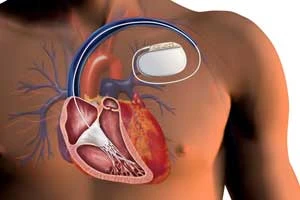

Pacemaker Implantation

Device implantation to regulate abnormal heart rhythms

ICD (Implantable Cardioverter Defibrillator)

Advanced device to monitor and correct heart rhythm